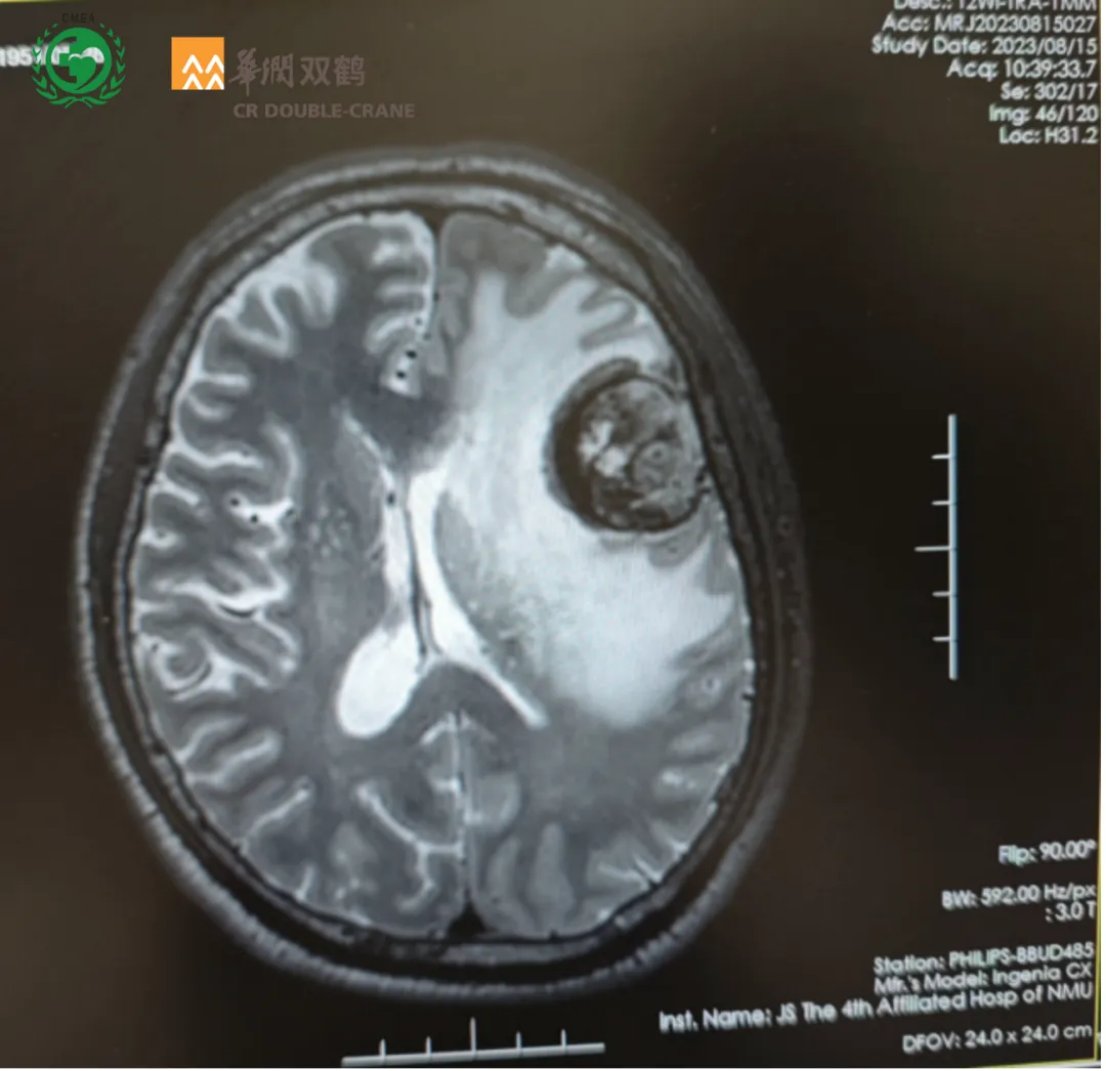

尽管患者后续未完全遵循放疗计划,但在长达8个多月的随访期间,多次复查头部MRI均显示脑内病灶稳定,局部已形成软化灶,未见复发迹象。这充分证明了含替尼泊苷方案在控制小细胞肺癌脑转移方面的持久疗效。

图4 第三次随访影像,病情稳定